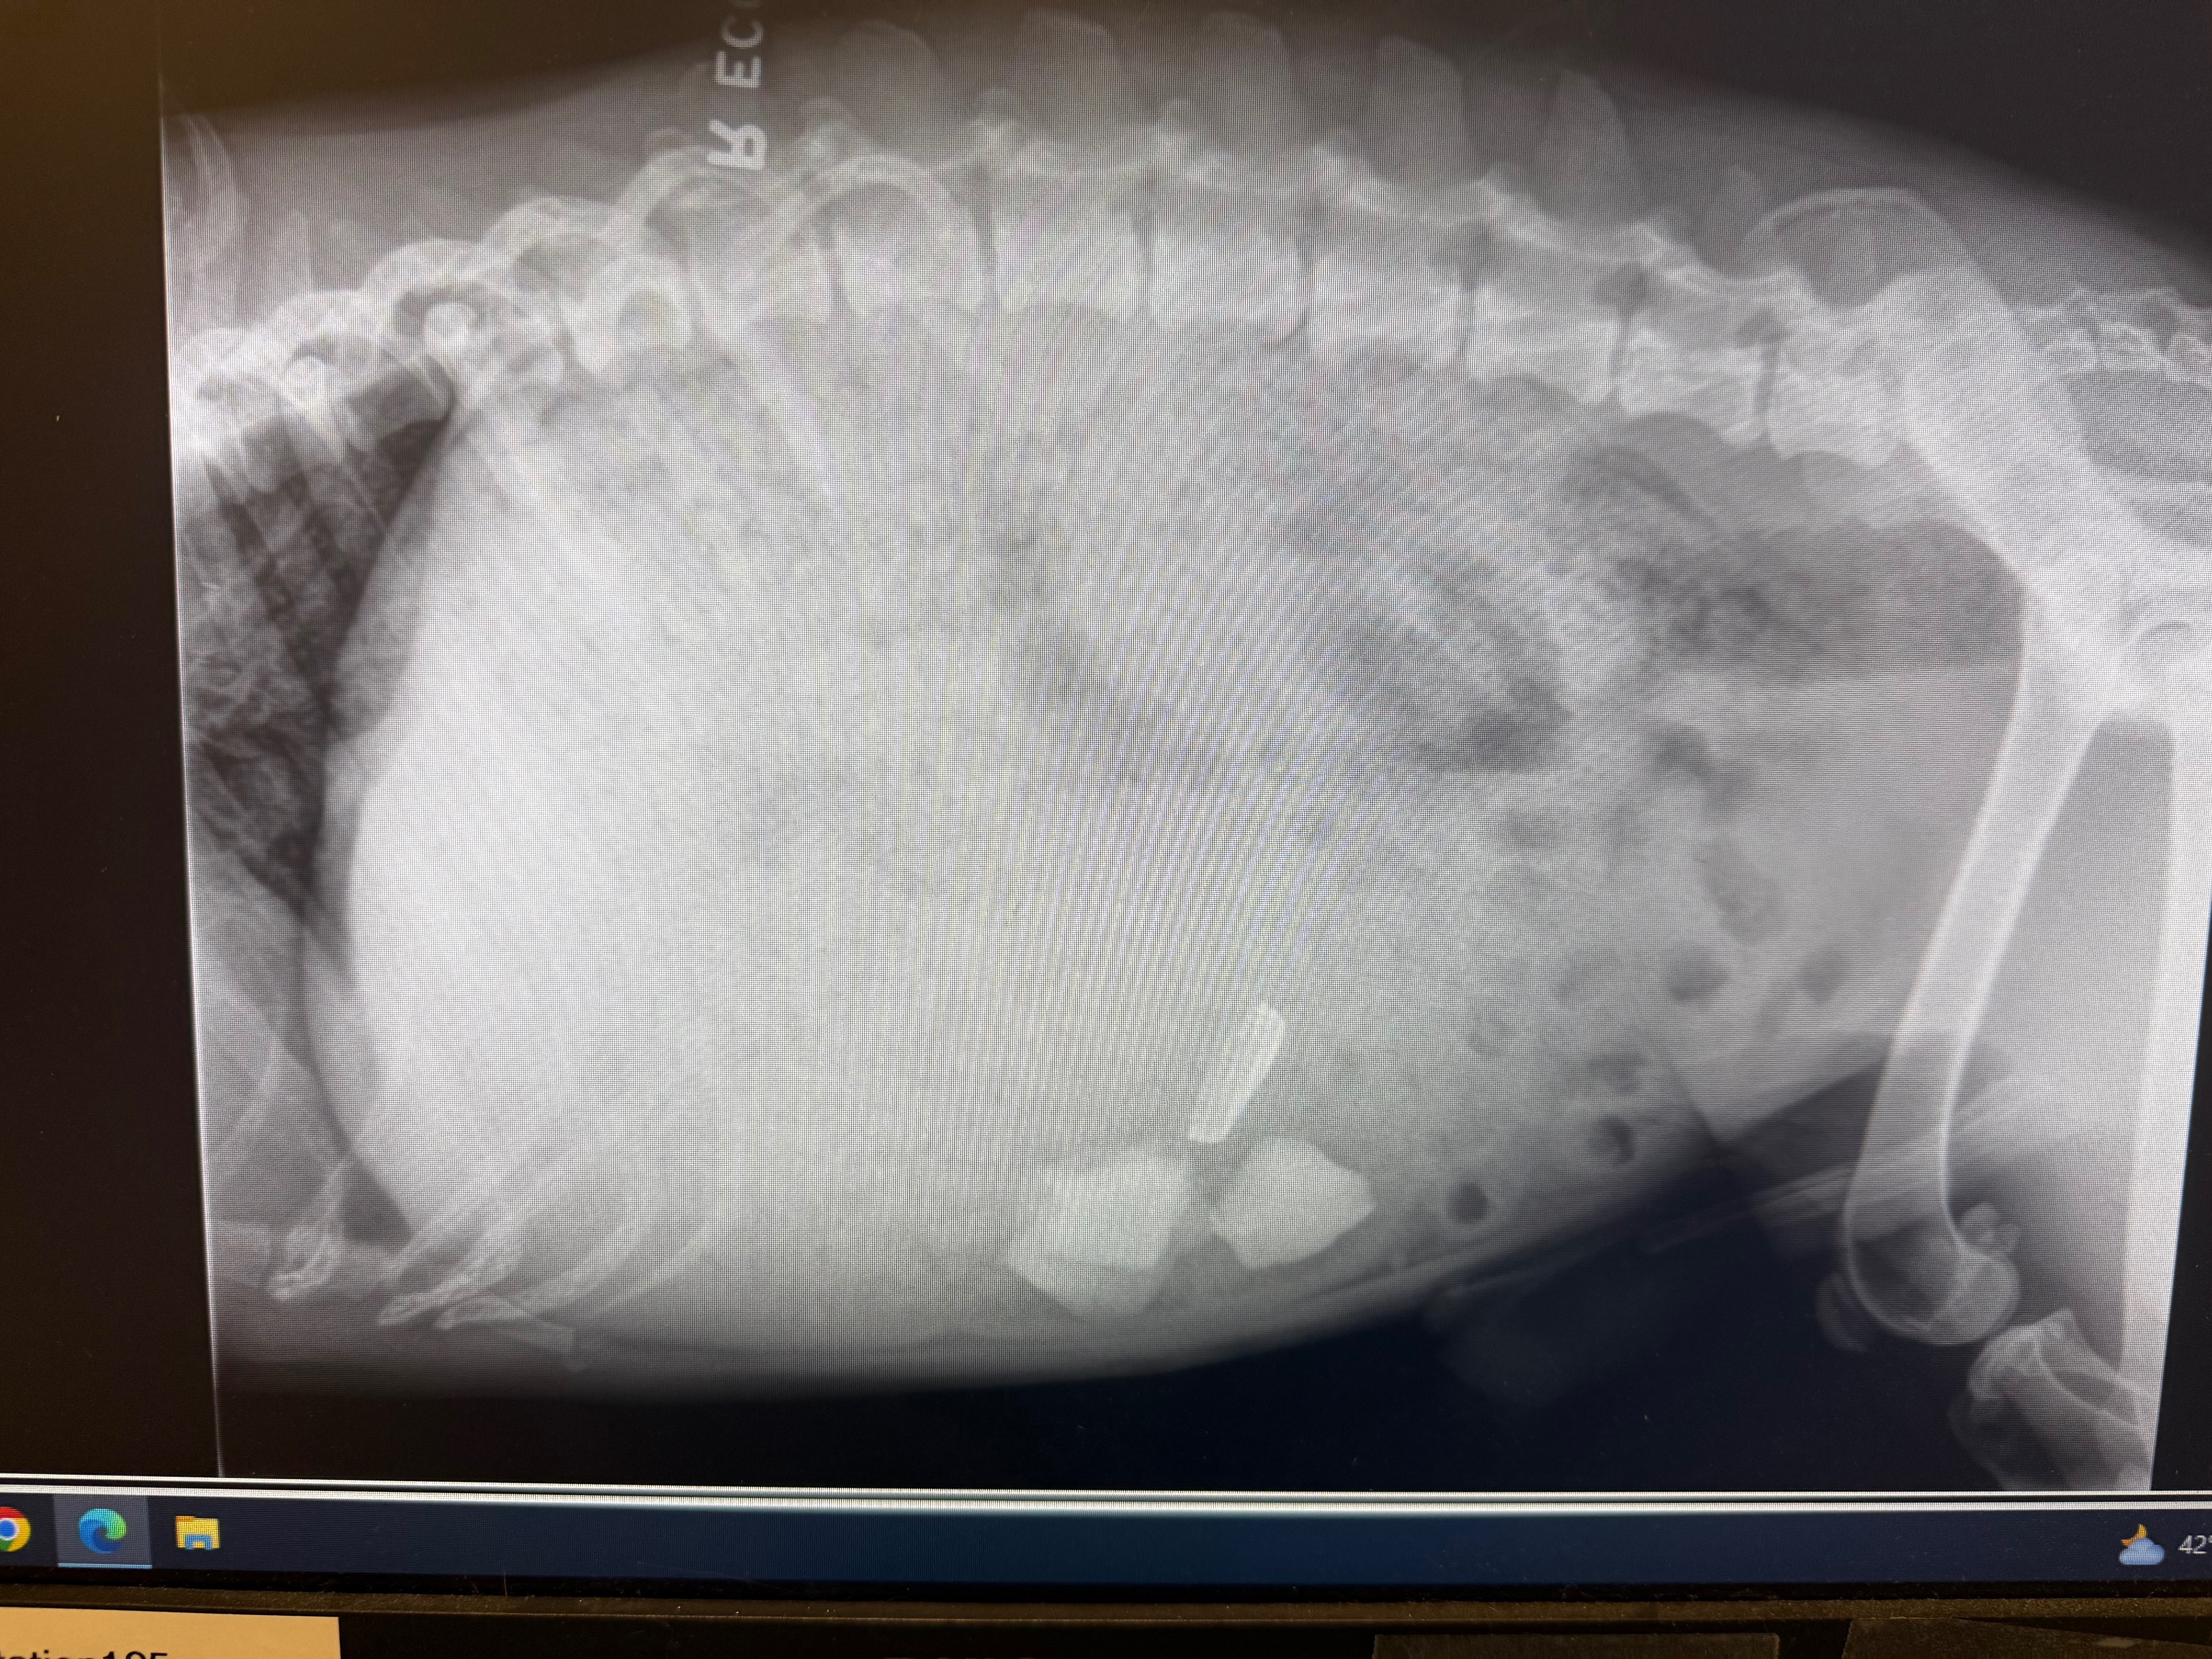

Hello, my name is Nico and recently I rescued a stray dog which I named Broly. He was found in a pretty tattered condition, malnourished, covered in wounds, with little life in his eyes. After about a week of being in my care, he is now full of life and making a great recovery, or so I thought. After a pretty tragic discovery, we found numerous pieces of sharp debris in his stomach. Any food he consumes from here on out will have a hard time making it passed said debris, and eventually ripping through his intestines if we don’t act fast. The vets are quoting upwards of 10k to save little Broly’s life.